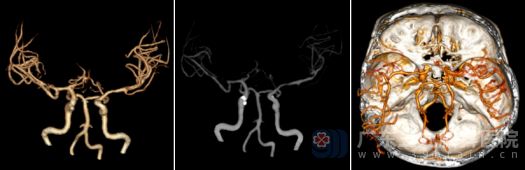

医生在高清显微镜下聚精会神“绣花”数小时,才将细小血管吻合成功。手术过程非常顺利。术后复查CTA显示:右侧颞浅动脉血管伸入颅内与右侧大脑中动脉远段吻合良好,桥血管显示清晰,局部皮层可见多发细小血管影,这意味着新建立的血液循环通路已经成功“接管”了部分供血任务。